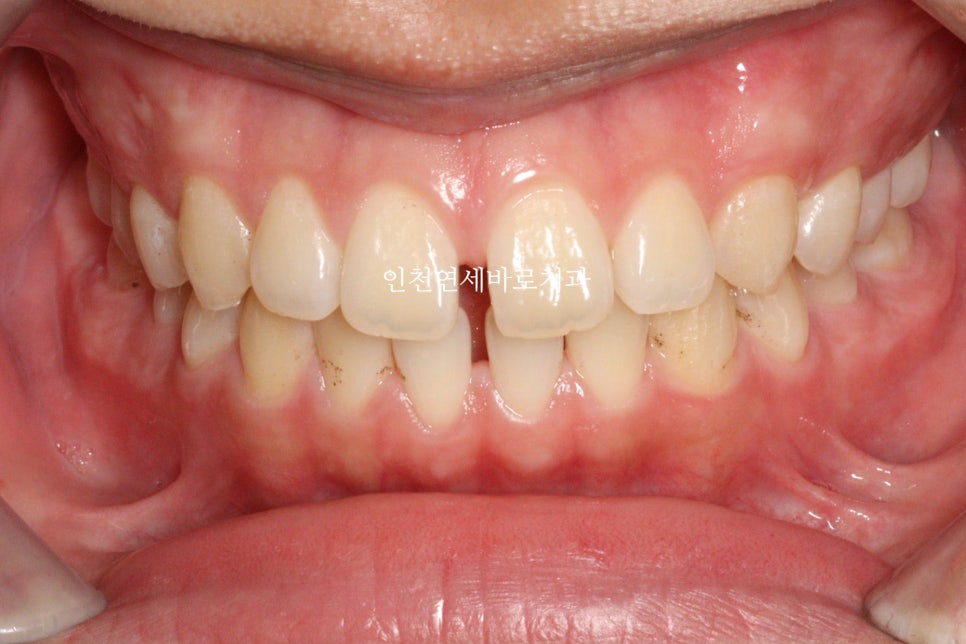

오늘은 아주 간단한 #벌어진앞니 케이스 하나 공유합니다

치아가 벌어져 오신 분입니다.

벌어진 앞니는 인비절라인의 가장 기초적인 치료 중 하나로, 치료 결과가 매우 좋은 편입니다. 이 케이스에서도 공간이 모두 닫히고 치아 배열이 개선되었습니다.